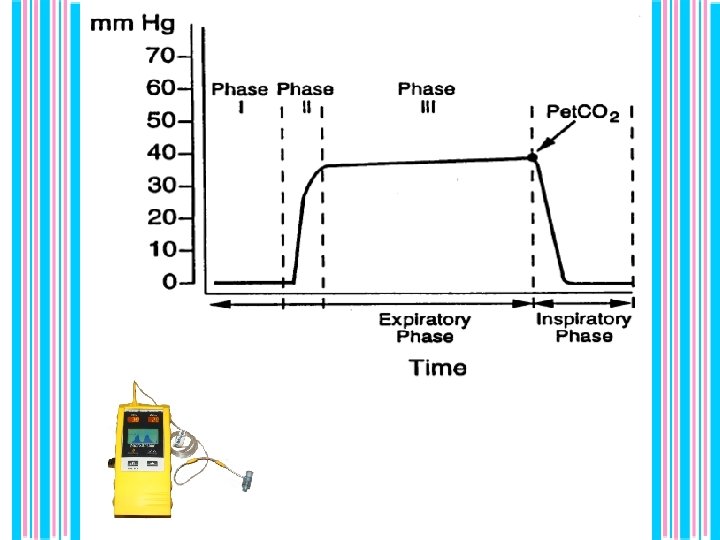

1 Place sensor & turn unit on. (unit will self-test) Confirm position by · CO 2 value (ideally > 20) · CO 2 waveform on monitor On/off ETCO 2 display Respiratory Rate Display

• False positive (tube in esophagus) • technical error. • False negative (tube in trachea CO 2 reading low) • severe bronchospasm, • hyperventilation, • technical error, • huge leak around ett, • cardiopulmonary arrest. _ _ _ Figure 1. Sensitivity = 94%, Specificity = 98%, P P Value = 98% , N P Value = 94%